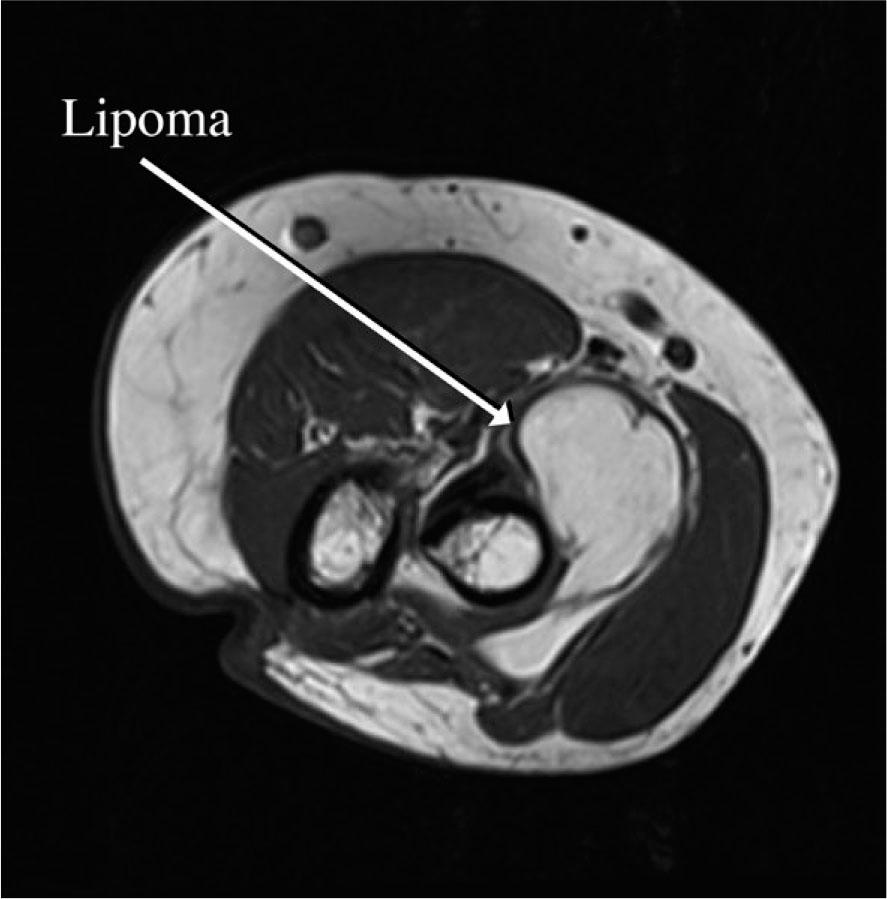

A 68-year-old female patient presented to the emergency room of our hospital with weakness of left wrist and fingers extension. In her past medical history, she reported having diabetes and arterial hypertension. The current symptoms had started 3 days prior to her visit. The patient mentioned strenuous work involving her arms due to cleaning, which included repetitive pronation and supination movements. A few hours after this activity she suddenly noticed weakness extending her fingers, without experiencing pain or paraesthesia. Clinical examination revealed weakness in left wrist extension accompanied by slight radial deviation (Muscle Power Scale - MRC 3) and more pronounced weakness in left fingers extension (MRC 2), the strength of other muscle groups of the left arm was preserved (MRC 5). There were no sensory deficits. To rule out possible brain vascular lesions brain computer tomography (CT) and CT angiography of cerebral arteries were performed, but the imaging did not show acute stroke or arterial narrowing. Based on these findings and patient's history a clinical diagnosis of left PIN palsy due to intrinsic entrapment caused by repetitive movements was made. Electromyography (EMG) performed a week after symptoms onset confirmed PIN lesion, showing denervation with fibrillations potentials and positive sharp waves (on scale 2 out of 3) and motor unit potential reduction in PIN innervated extensor indicis proprius muscle, brachioradial muscle did not show any signs of denervation. The superficial sensory radial nerve conduction study was normal. At the follow-up visit after 4 weeks, there was no improvement of muscle strength. Consequently, we decided to perform a magnetic resonance imaging (MRI) scan of the left elbow, which revealed a 50 x 40 x 25 mm lipoma as a probable cause of nerve compression (Figure 1). The patient included in this study provided written informed consent for the publication of anonymized data in accordance with the declaration of Helsinki.

MRI of left elbow.